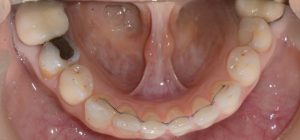

הקיבוע המודבק עשוי לרוב מחוט מתכתי ומותאם לצורת השיניים והוא כולל את ששת השיניים הקדמיות. החוט מודבק בד"כ לצד הפנימי של השיניים ומחבר בינם ועל ידי כך מונע את תזוזתם. יתרונו הוא בכך שאינו כרוך בשיתוף פעולה של המתרפא/ה והוא מבטיח את יציבות התוצאה. חסרונו הוא שהוא עלול להישבר עם השנים, לצבור שאריות מזון ואבנית ויש צורך בהורדתו בזמן טיפולים בשיניים אליו הוא מחובר. כאשר קיבוע מתנתק יש לבדוק מהן הסיבות שגרמו לכך ולעיתים אין אפשרות להדביק קיבוע חדש בגלל שינויים בסגר של המטופל.  יש להקפיד היטב על ניקוי השיניים סביב הקיבוע. רובד ואבנית עלולים להצטבר מתחת לחוט המודבק  ולגרום לדלקות חניכיים. לניקוי יעיל יש להשתמש בעזרים נוספים למברשת השיניים כגון חוט וקיסמים דנטלים מיוחדים. הסבר והדרכה יינתנו במרפאה. יש להקפיד על ביקור אצל שיננית אחת לארבעה חודשים ובמהלך הטיפול יש לוודא שהקיבוע מודבק היטב ואינו רופף וזקוק לתיקון.

קיבוע 1 (640x371)